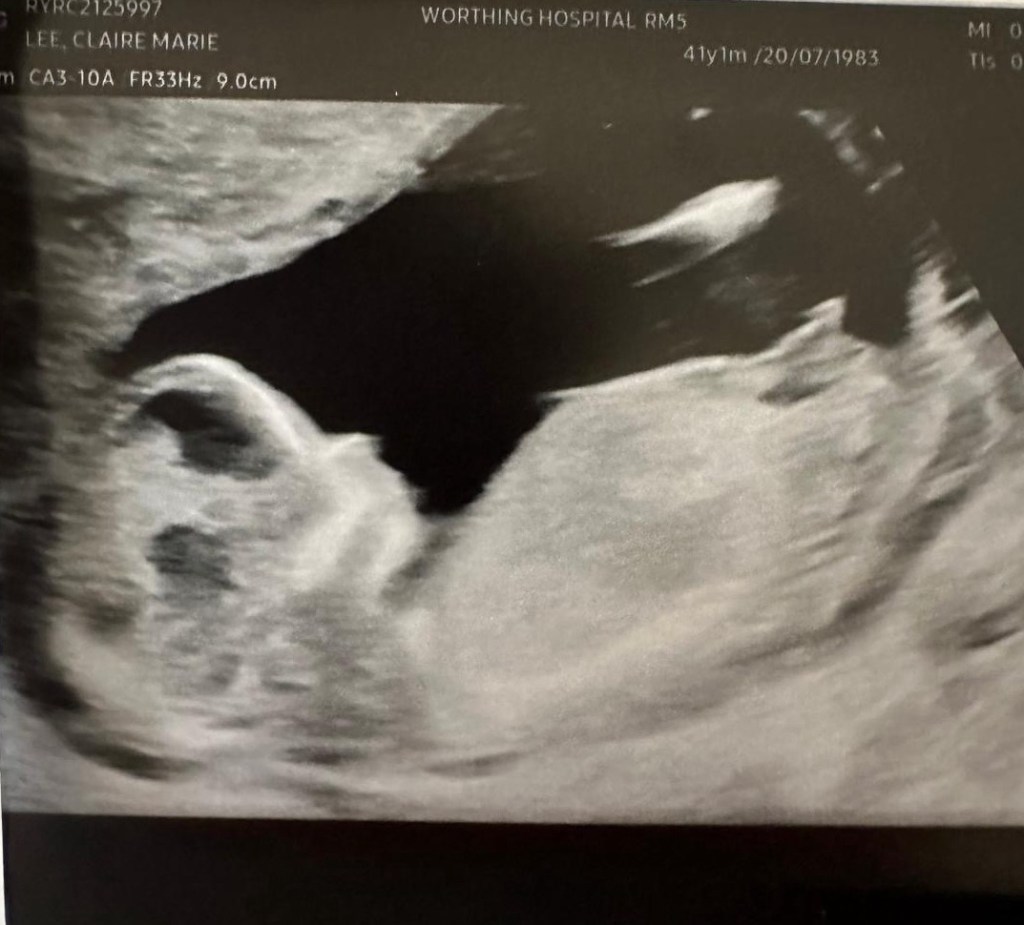

We’re having a baby!

It was a nearly 8 years ago that our last baby arrived to share our world, and nearly 12 years ago that our big boy was born. You can imagine our surprise and joy of finding out that we have another little bun baking away!

We’re so excited to meet our new little one when they arrive in spring and share our love and life with them. In the meantime we’ll be spending our first winter in England for a long time, snuggling down and preparing for our next adventures happening in 2025.